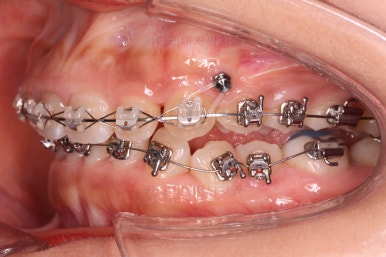

앞니쪽에는 미니스크류를 식립했는데요.

과개교합 개선, 교합 개선, 거미스마일(잇몸웃음) 개선 등 여러 가지 목적을 동시에 달성할 수 있어요.

위쪽은 미니스크류 위치를 바꿔줘 교합을 맞춰주고요.

아래쪽은 마찬가지로 미니스크류를 비대칭으로 식립해서 어금니를 당겨줍니다.

계속 당겨줍니다.